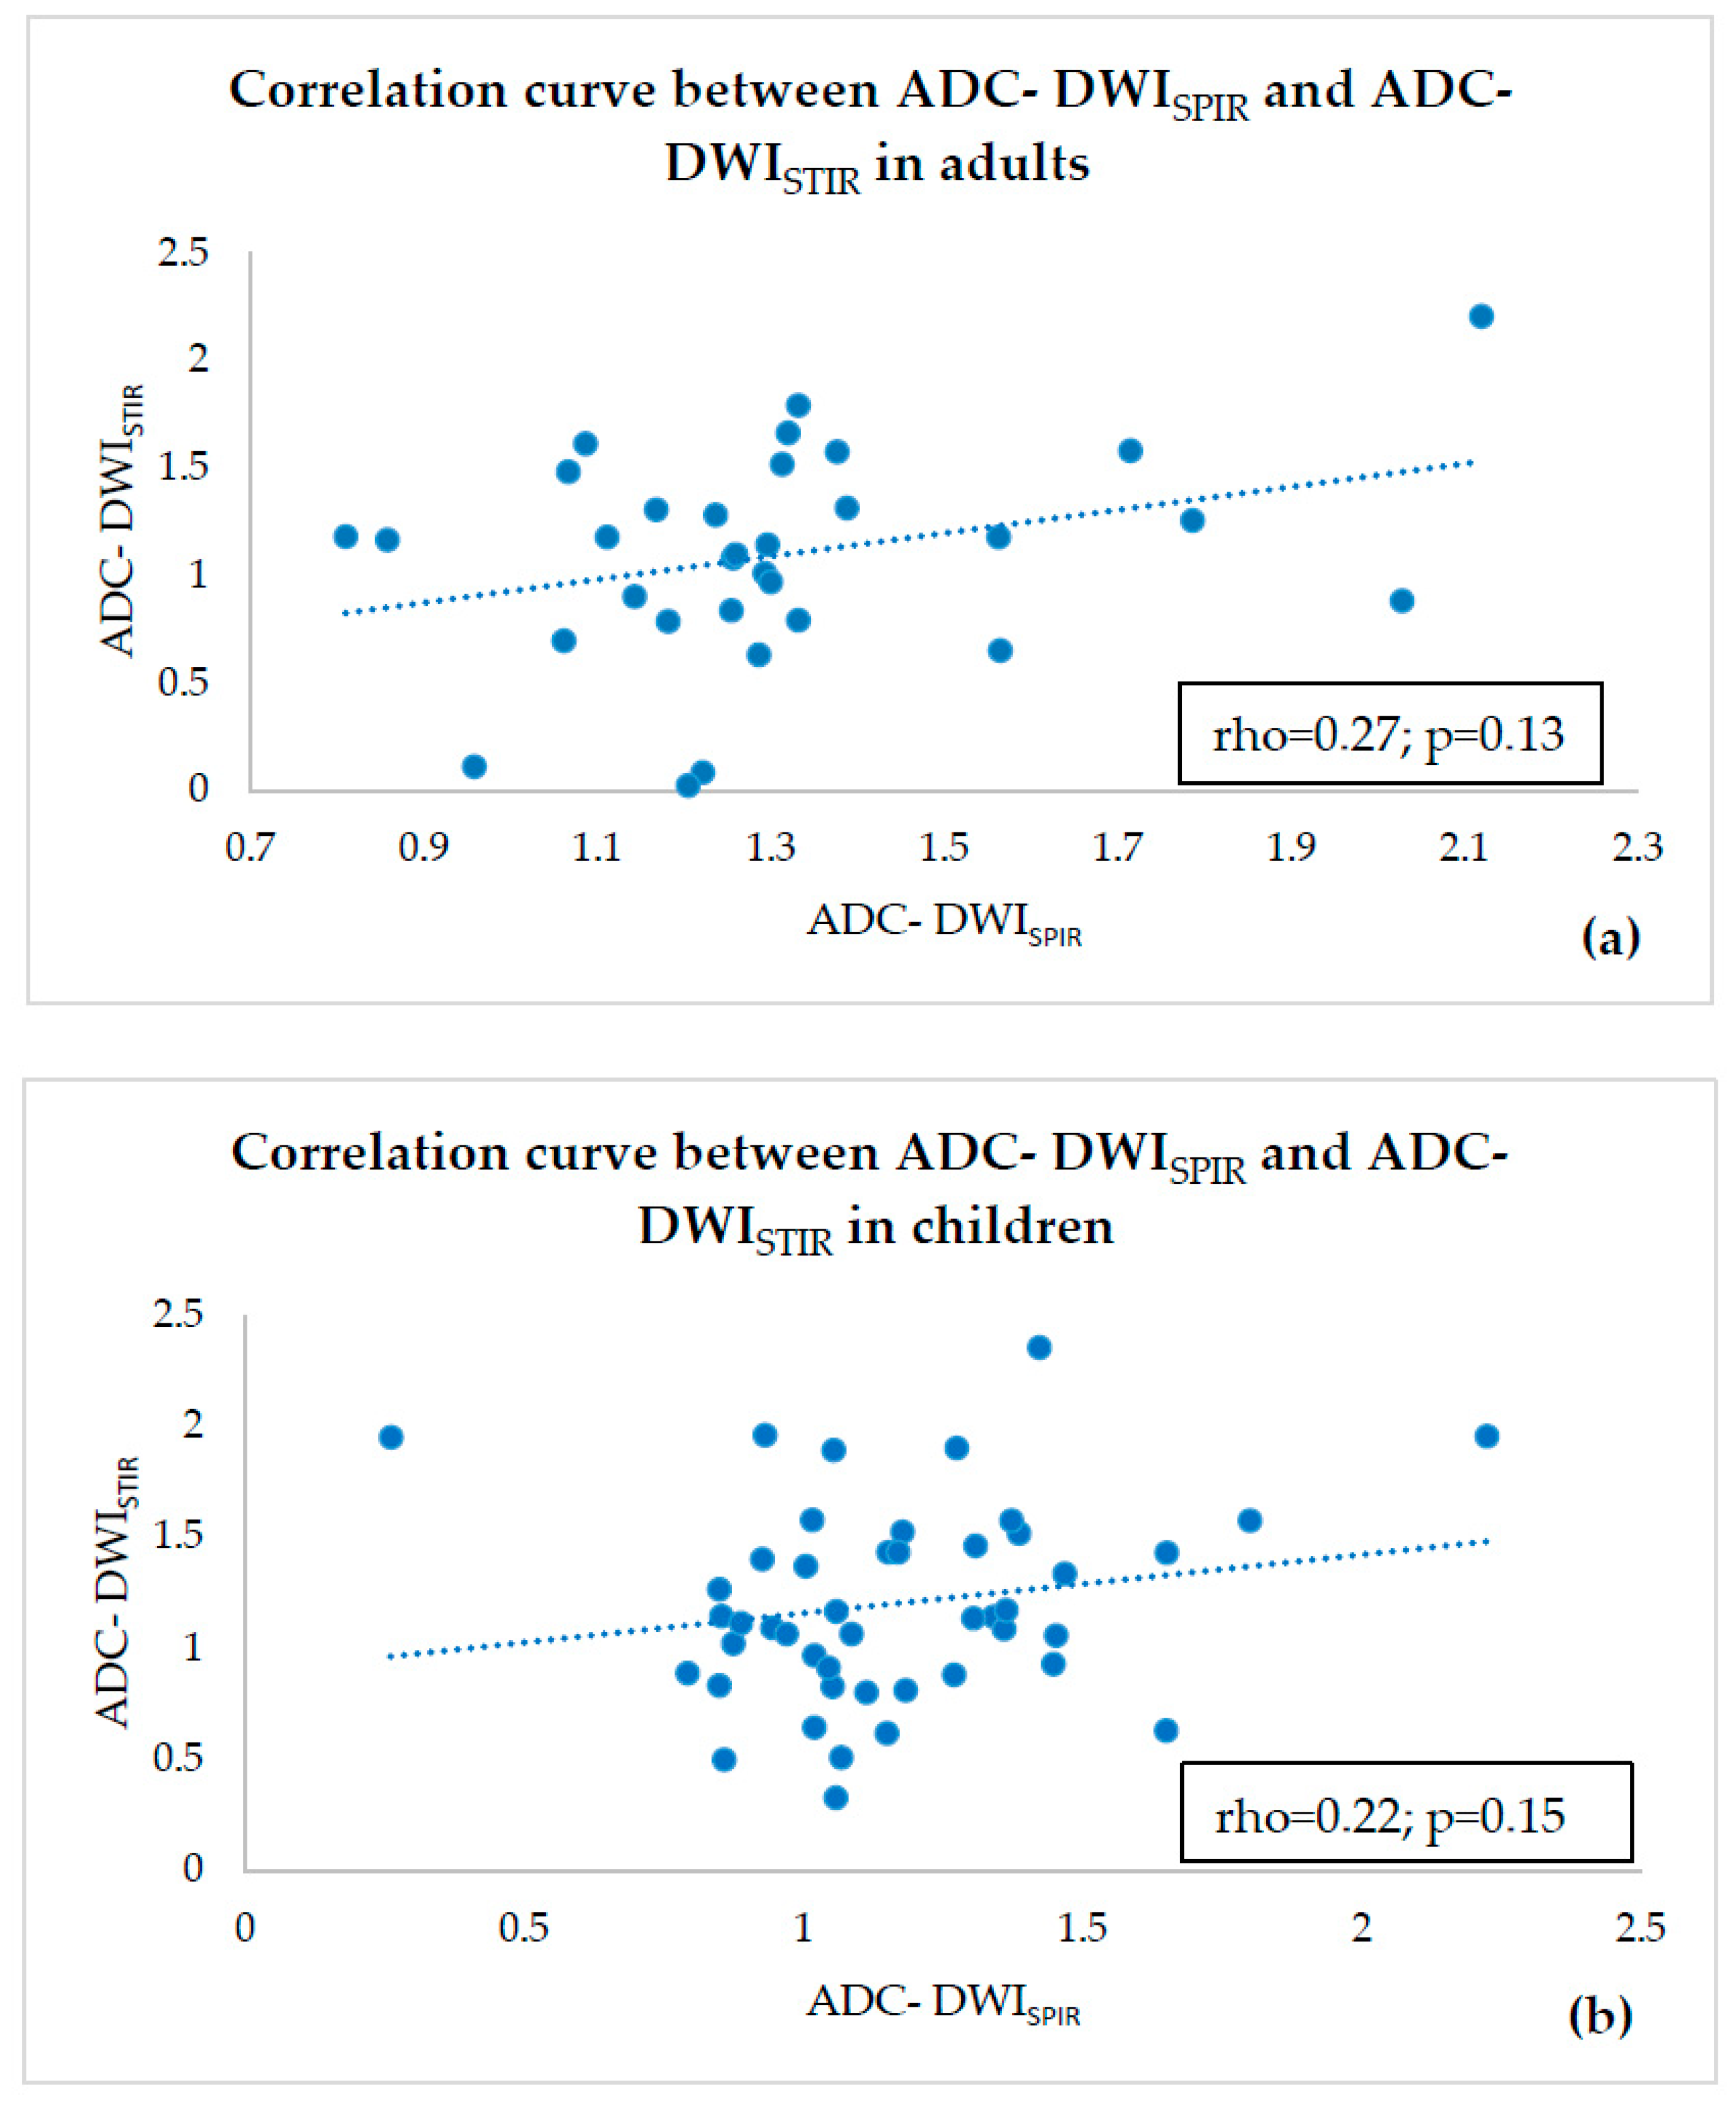

- ADC values of both adults and children were compared within a single fat suppression technique, and we observed statistically significant ADC-DWISPIR difference between adults and children (1.31 × 10−3 mm2/s, SD 0.29, vs. 1.16 × 10−3 mm2/s, SD 0.31; p = 0.02), with 12.12% lower ADC values in children compared to adults, but no statistically significant difference between the ADC-DWISTIR values in adults and children (1.09 × 10−3 mm2/s, SD 0.49, vs. 1.20 mm2/s × 10−3, SD 0.44; p = 0.38);

- both DWISPIR and DWISTIR techniques were compared within one patient group, both in adults and children. In this case, the analysis showed difference of 16.73% between ADC-DWISPIR and ADC-DWISTIR values in adults, being lower in DWISTIR (1.31 × 10−3 mm2/s, SD 0.29, vs. 1.09 × 10−3 mm2/s, SD 0.49; p = 0.03), but did not show difference between ADC-DWISPIR and ADC-DWISTIR values in the children’s group (1.16 mm2/s × 10−3, SD 0.31, vs. 1.20 × 10−3 mm2/s, SD 0.44, p = 0.97).